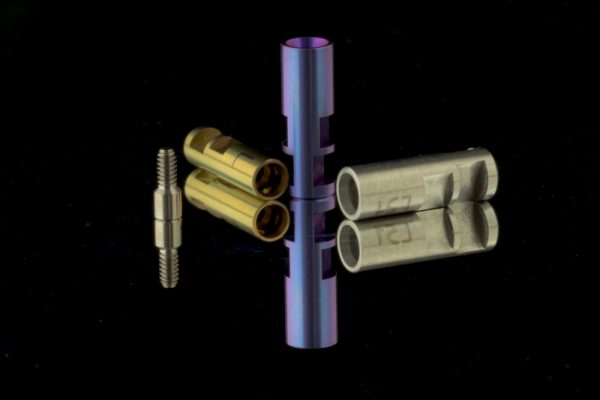

Implantat-Prothetik

- Bohrschablone

- Individuelle oder konfektionierte Abutments aus Metall

- Individuelle oder konfektionierte Abutments aus Keramik

- Zementierbare oder okklusal verschraubte Implantatkronen, -brücken oder -teleskope

- Stege, Teleskoptechnik, Locator